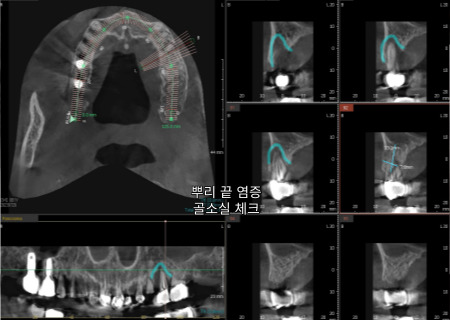

3D CT와 구강 스캔을 통해

사진처럼 3차원의

해부학적 구조를

관찰하는 모습입니다.

특히 위턱의 경우

입천장 부근에 있는

얇은 상악동 막이 존재해

다치지 않도록

심는 위치와 뼈상태를

정밀하게 살펴야 합니다.